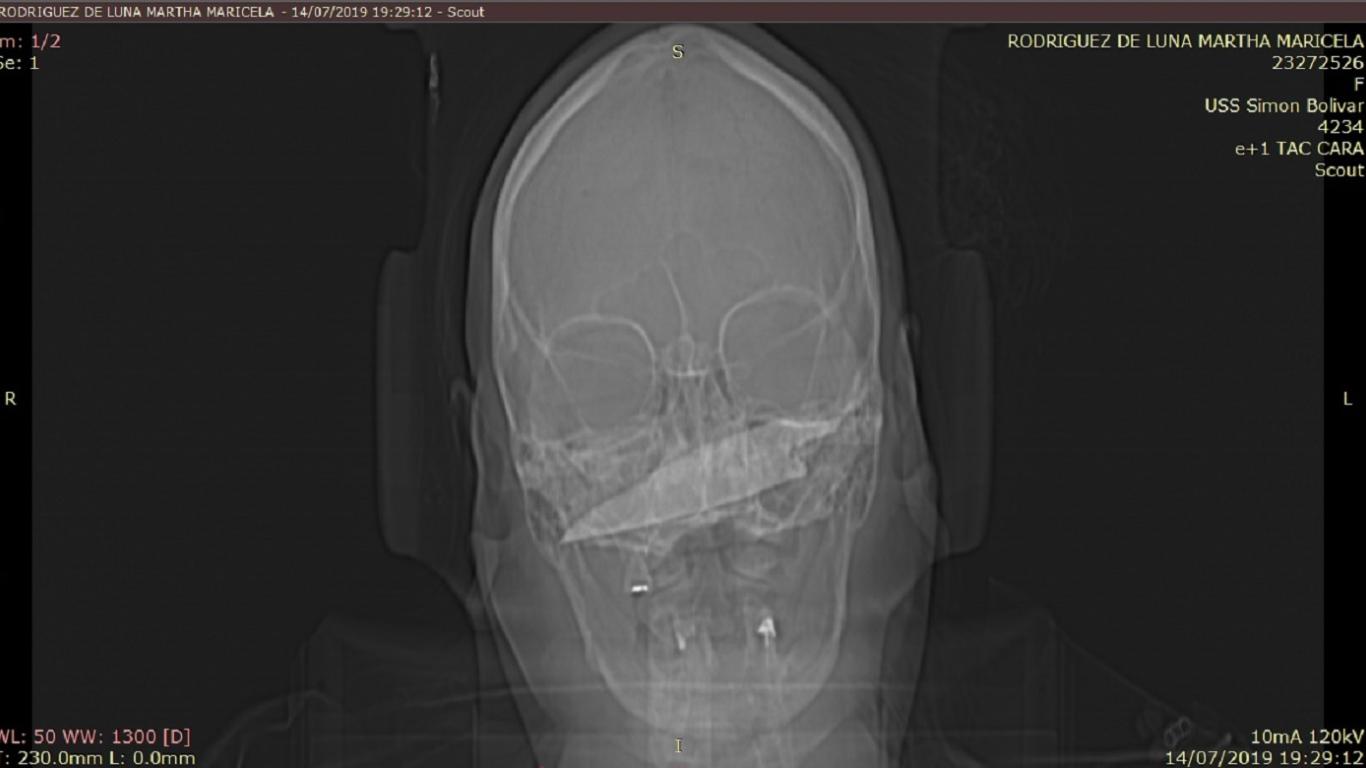

Luego de sufrir una herida en su rostro con arma blanca, médicos del Hospital Simón Bolívar reconstruyeron la cavidad nasal de una mujer de 67 años. Según su testimonio, fue víctima de esta agresión mientras caminaba por una vía de norte de la ciudad. El cuchillo que tenía un diámetro de 15 centímetros fue retirado de su mejilla.

“Apenas la paciente ingresó al servicio de urgencias se verificó que estuviera hemodinámicamente estable y se procedió a realizar la cirugía para extraer el elemento. Se controló el sangrado y afortunadamente los vasos sanguíneos de alto calibre no fueron afectados por pocos milímetros”, narró Natalia Novoa Robles, médica del hospital.